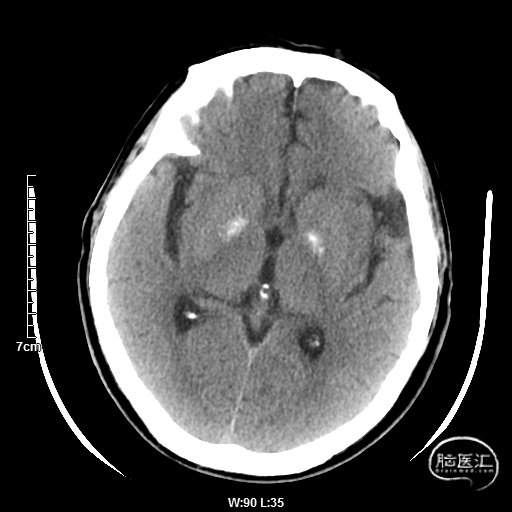

术后造影:

血管再通,前向血流3级。左侧为胚胎型大脑后。

术后用药:替罗非班24小时复查CT后桥接双抗。

术后CT:未见明显脑出血,双侧小脑低密度影。

术后CTA:Bridge药物支架形态良好,前向血流良好。